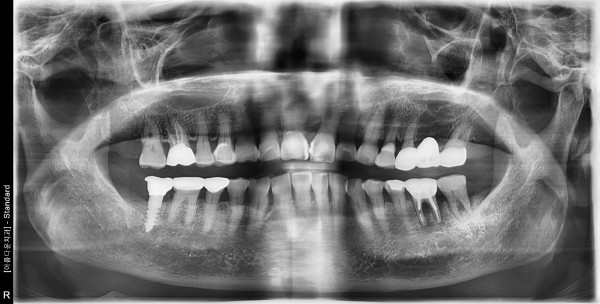

84세 여자환자 / 좌측 구치부 발치후 뼈이식 및 임플란트식립